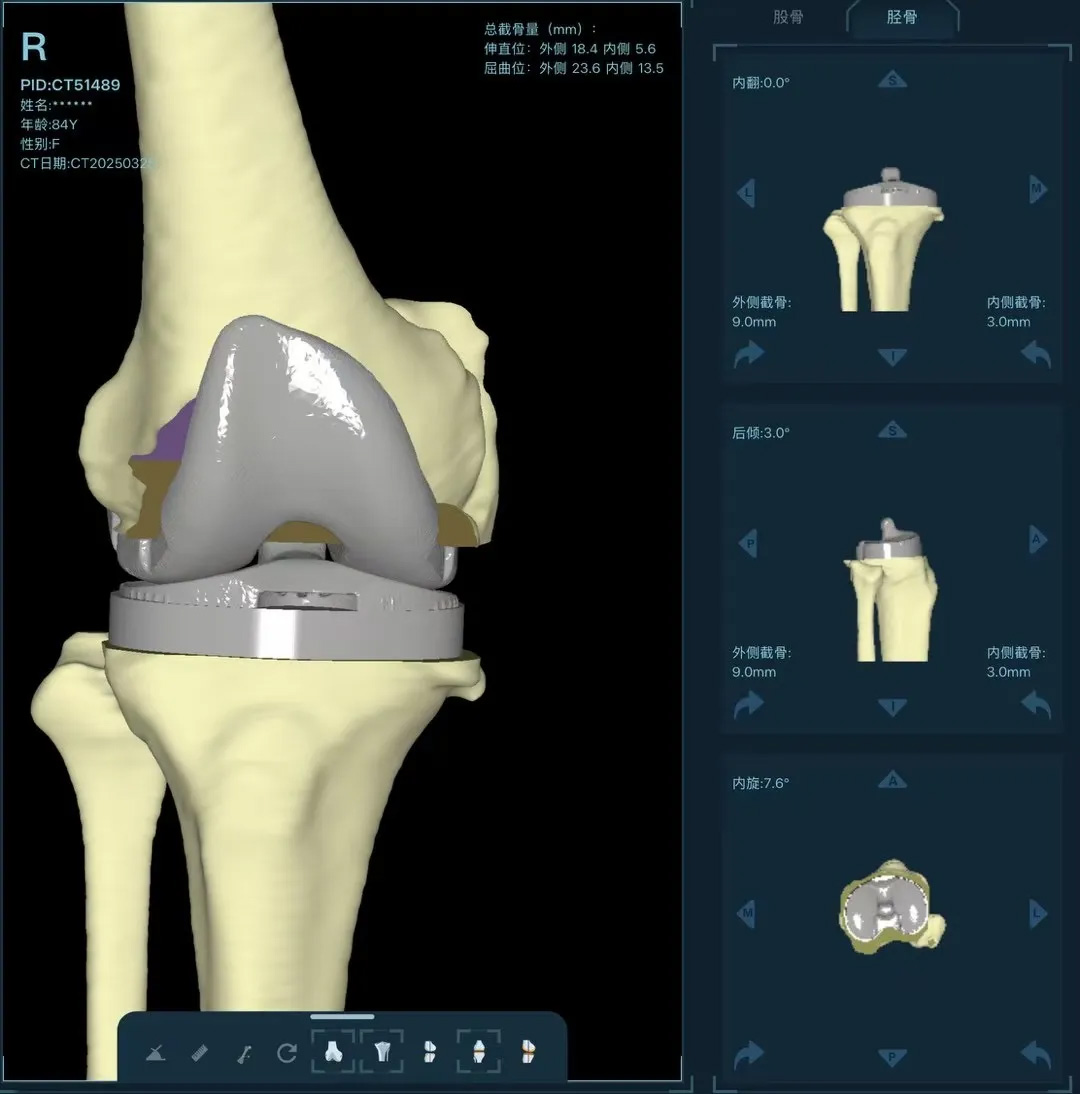

在家人幾乎放棄希望時,AI三維規(guī)劃技術(shù)為這場"關(guān)節(jié)保衛(wèi)戰(zhàn)"帶來轉(zhuǎn)機(jī)。

術(shù)前:AI通過CT掃描生成毫米級膝關(guān)節(jié)三維模型,為假體安裝設(shè)計出誤差小于1毫米的精準(zhǔn)方案

圖片